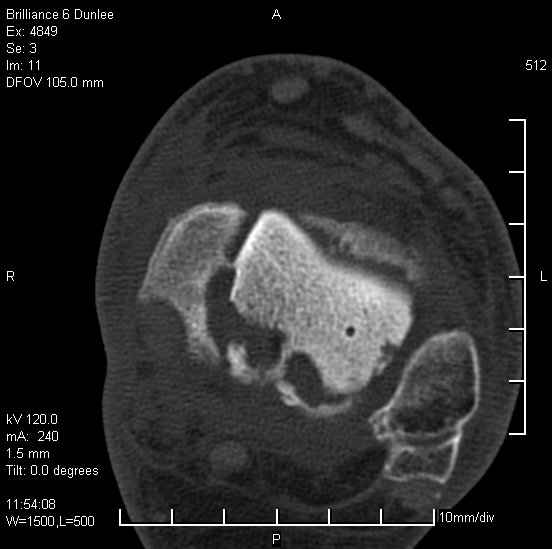

На лечении находится пациент 35 лет. Травма в сентябре 2008 г.- открытый вывих таранной кости

В день травмы ПХО, вправление вывиха, трансартикулярная фиксация. Рана зажила первично. С января нагрузка на конечность. С конца апреля- болевой синдром. На рентгенограммах и КТ признаки ас. некроза таранной кости, артроз подтаранного и голеностопного суставов.